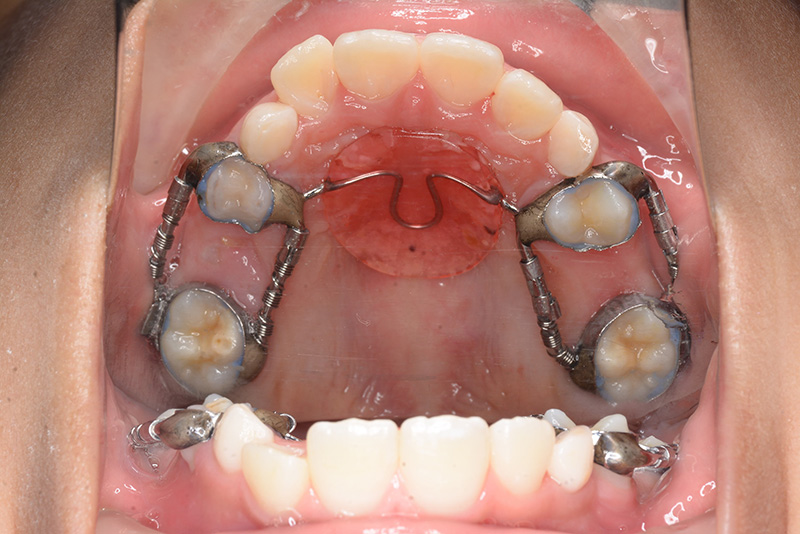

| 使用装置 | GMD、Nanceホールディングアーチ | ||||||

| パノラマ所見 | 上顎両側6、特に左側6は近心傾斜が認められ、両側5の萌出スペース不足が認められた。 |

| 批評・予后 | 早期に6の遠心移動を行いナンスのホールディングアーチにて保隙をした結果、5は良好な状態で萌出できたように思う。 今後は永久歯列完成まで経過観察を行っていく予定である。 |